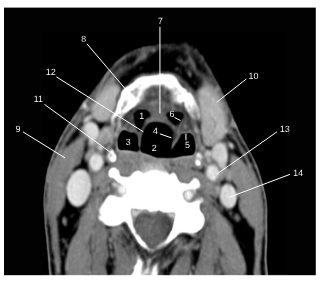

Fig. 62.6 Étage supraglottique : scanner, coupe transversale.

1. Vallécule épiglottique droite. 2. Lumière laryngée. 3. Récessus piriforme droit. 4. Pli ary-épiglottique. 5. Pli pharyngo-épiglottique. 6. Pli glosso-épiglottique latéral. 7. Pli glosso-épiglottique médian. 8. Os hyoïde. 9. Muscle sternocléidomastoïdien. 10. Glande submandibulaire. 11. Corne supérieure du cartilage thyroïde. 12. Épiglotte. 13. Artère carotide. 14. Veine jugulaire interne.